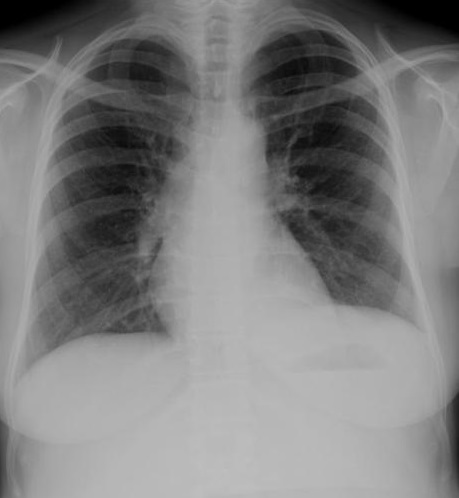

Image

radiologique du cliche de face PA d'une pleuresie de

moyenement abondance en aspect de opacite basale

non systematise , n'a pas de bronchogram aerique .

La courbe superieure est nette et incline dehors en

dedans vers à inferieure du poumon , concave à

inferieure en connue sous nom de "courbe parabolique

de Damoiseau " . |